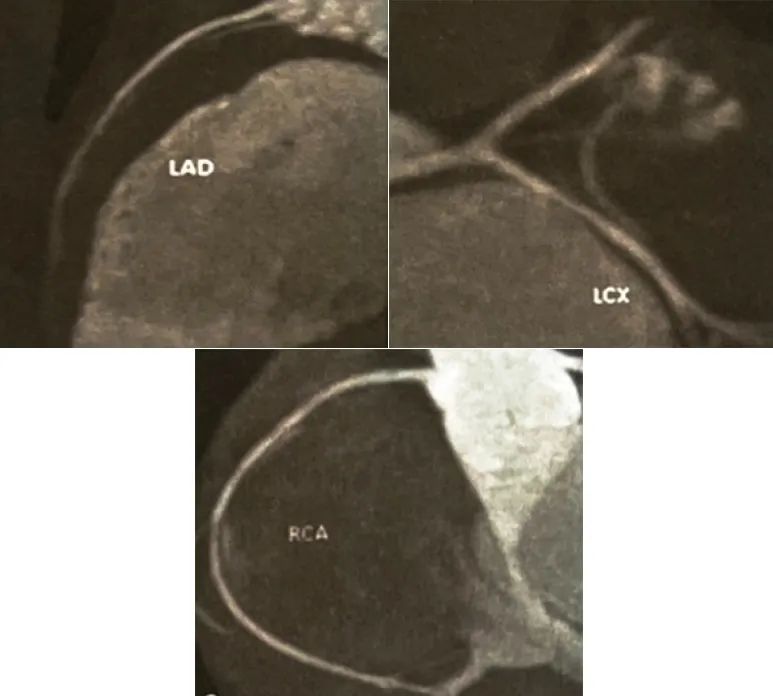

综上,目前主要需进一步鉴别冠状动脉炎-川崎病及冠状动脉起源引起的急性心肌梗死及心肌炎,考虑患者年龄小,需评估冠状动脉起源问题,遂入院后行立即行急诊冠状动脉CTA评估冠状动脉情况,结果显示(图1)冠状动脉起源正常,未见狭窄、扩张及血栓形成,故可排除川崎病及冠状动脉起源异常导致的心肌缺血,初步诊断为急性心肌炎。

图1、冠状动脉CTA:冠状动脉未见明显狭窄及扩张,起源及走行无异常